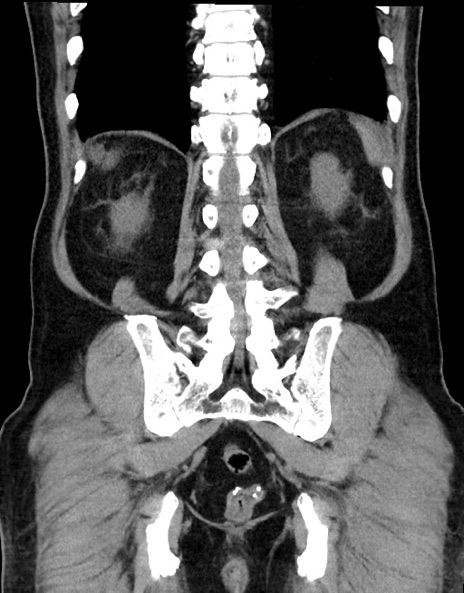

症例15(冠状断像)

【症例】70歳代男性

【主訴】腹痛

【現病歴】今朝から腹痛あり。全体的に痛い。特に左上の方。排ガスが今日はない。冷や汗が出る。

【既往歴】直腸癌術後

【身体所見】左側腹部〜上腹部に圧痛あり。腹膜刺激症状明らかなではない。軽度反跳痛。左下腹部に術後瘢痕あり。

【データ】WBC 7700、CRP 0.02

横断像